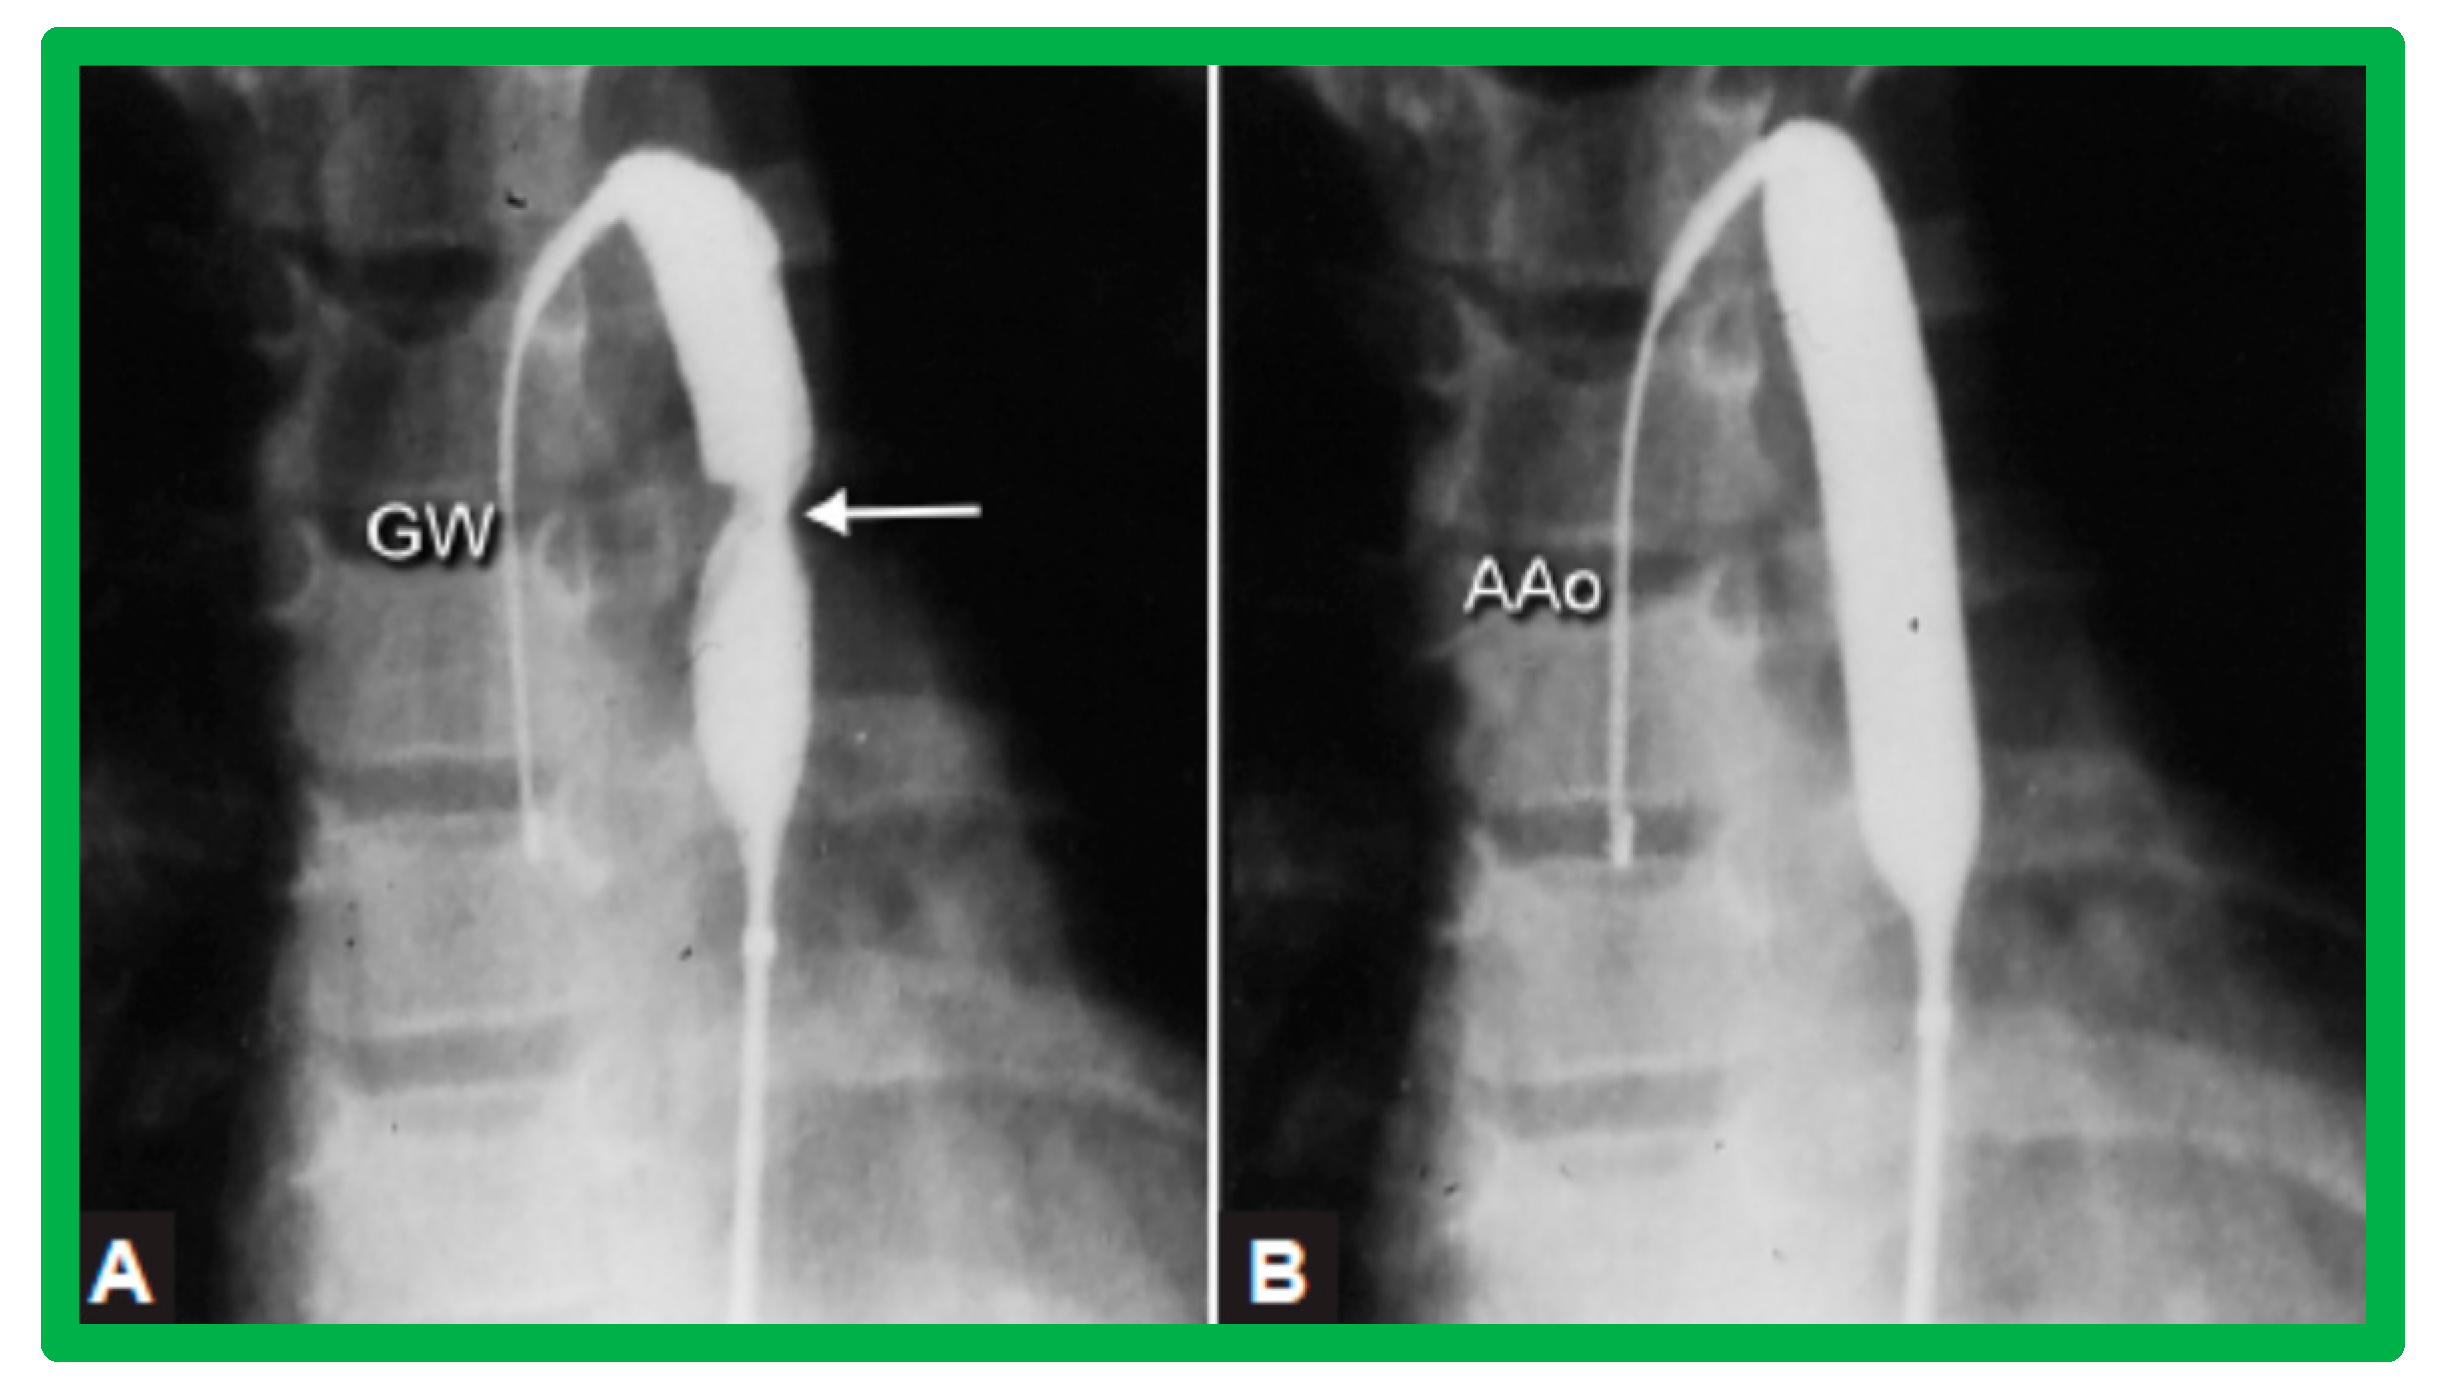

3.3. Aortic Coarctation, Native

Revisit BA in the Neonate and Young Infant